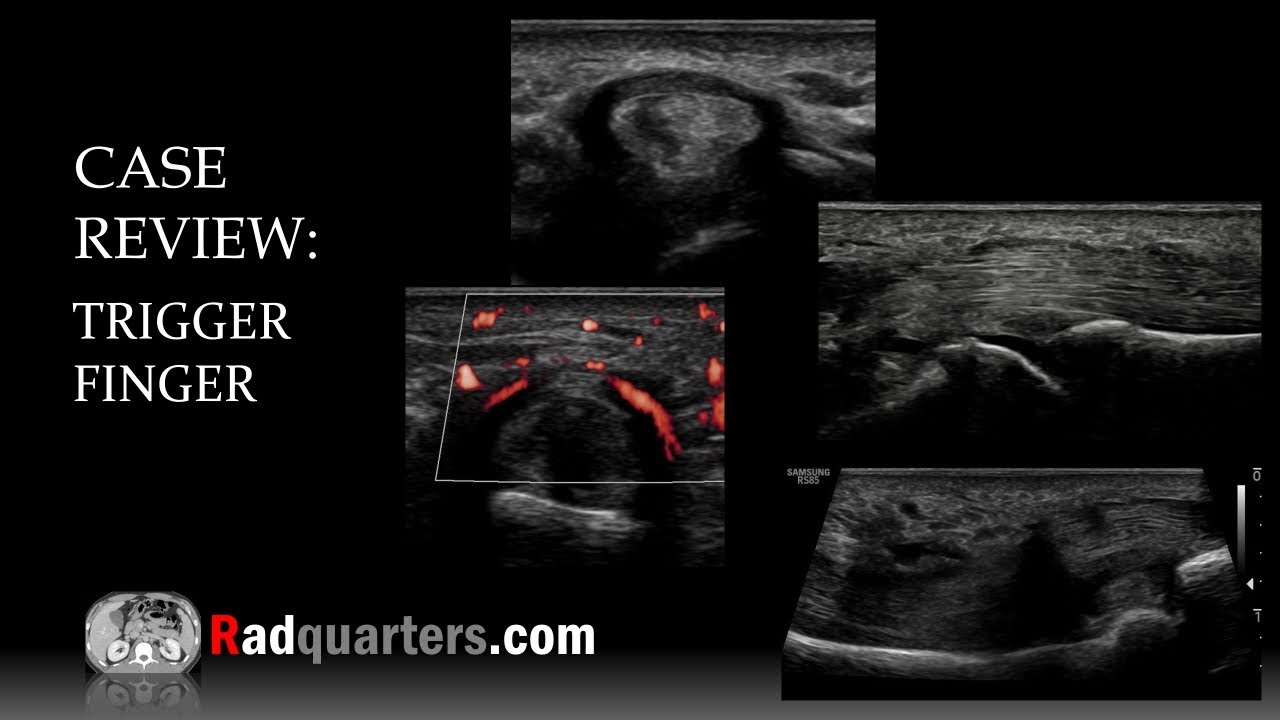

Ultrasound Of Trigger Finger Stenosing Tenosynovitis YouTube